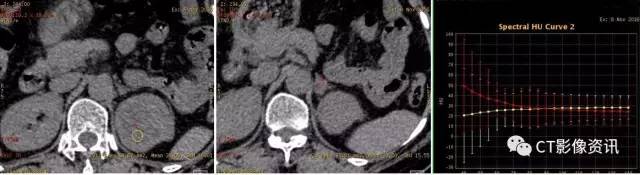

病例资料 患者女性,58岁,既往体健,查体发现左肾占位,行泌尿系CTU扫描,左肾占位呈典型“快进快出”强化方式(图1),考虑肾癌,透明细胞癌可能性大。左肾上腺见结节灶,呈明显均匀强化(图2),肾上腺转移瘤待排,行能谱CT检查。

图1:左肾占位,增强扫描皮质期不均匀明显强化,实质期持续强化,延迟期造影剂退出呈低密度,为典型肾癌的CT表现。